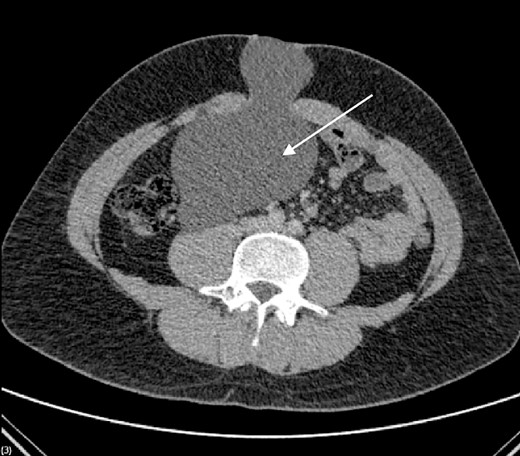

We present the case of a 26-year-old man who presented to the general surgery outpatient clinic with intermittent peri-umbilical pain, and the presence of a soft swelling palpable at his umbilicus. There was a positive cough impulse consistent with a true umbilical hernia and the patient described no previous medical or surgical history. An abdominal ultrasound scan visualized a large thin-walled serous fluid collection tracking into the peritoneal cavity (95 mm × 87 mm × 97 mm) (Fig. 1). Computed tomography (CT) of the abdomen and pelvis with contrast reported a large bi-lobed cystic mass centred at the right side of the mesentery, with herniation of part of the cyst along the umbilicus. Displacement of the small bowel with anterior extension into the abdominal wall was seen with the suggestion of posterior extension into the right retroperitoneal space (Figs 2 and 3). The patient underwent routine pre-operative work up and the cyst was excised through a midline para-umbilical laparotomy (Fig. 4) given the concern of retroperitoneal involvement. Intra-operatively, the hernia neck and the root of the cyst were found at the base of the umbilical cicatrix with no attachment to the mesentery. The cyst was loculated and filled with clear fluid. It was dissected off the peritoneal tissues and off from the posterior umbilical skin prior to removal. There was evidence of rupture of one of the locules and clear fluid was drained.

PIC was excised through midline laparotomy given the suggestion of retroperitoneal involvement on pre-operative imaging.